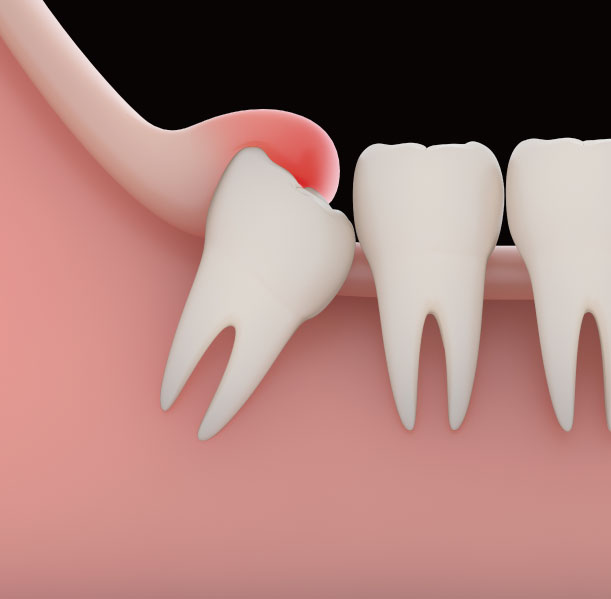

사랑니는 우리 입속에 가장 뒤에 난 어금니를 말하며, 전문용어로 설명해 드리면 제3대구치라고 하며 얼굴을 중심으로 좌우로 8번째 자리하고 있는 치아를 말합니다. 사랑니는 사춘기 이후에 자란다고 합니다. 사춘기에는 여러 가지 감정을 느끼게 되고 그 감정 중 하나가 사랑이라는 감정이지요. 그래서 이 치아를 사랑니라고 부른다고 합니다.

치과 치료를 하면 알 수 있는 것이 치아는 함부로 뽑지 않습니다. 정말 최대한 살려보고 그래도 안 되면 뽑아서 임플란트 등으로 빈자리를 채웁니다. 사랑니는 다른 치아들과 달리 발치를 해야 할 때도 있습니다. 잘 자란 사랑니는 특별한 문제를 일으키지 않아 뽑지 않아도 됩니다. 하지만 대부분의 사랑니는 말썽을 부립니다. 출혈, 염증, 통증 및 악취, 충치 들 여러 가지 문제를 일으킬 확률이 높기 때문에 뽑아야 합니다.